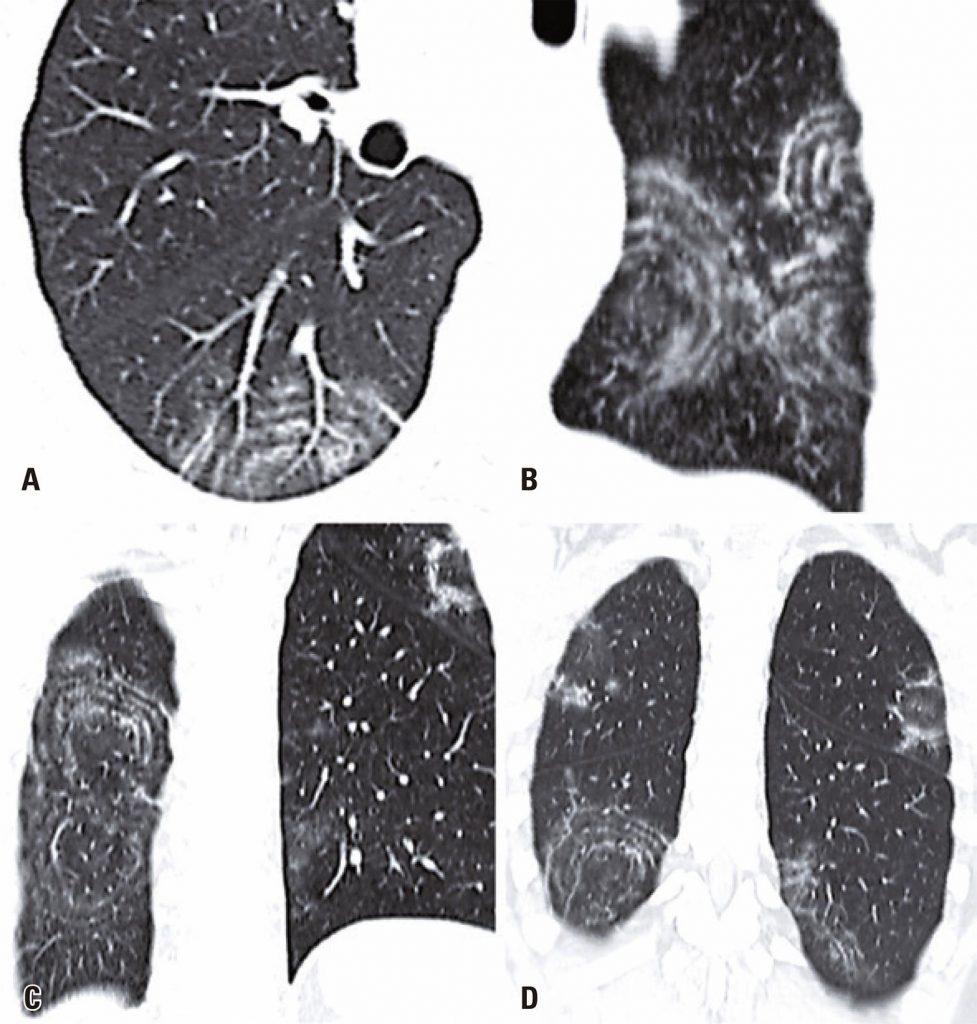

Um homem de 49 anos procurou nosso pronto-socorro com história de 2 dias de febre, tosse, anosmia, ageusia e odinofagia. Sua história pregressa incluía hipertensão. No momento dessa apresentação, a tomografia computadorizada de tórax revelou opacidades em vidro fosco periféricas e bilaterais, com algumas linhas intralobulares visíveis, ou seja, achados típicos de pneumonia causada pelo coronavírus da síndrome respiratória aguda grave 2 (SARS-CoV-2). Além disso, alguns achados revelaram o sinal do alvo (). O tratamento de suporte do paciente foi continuado, e a reação em cadeia da polimerase via transcriptase reversa (RT-PCR) confirmou a infecção por SARS-CoV-2.